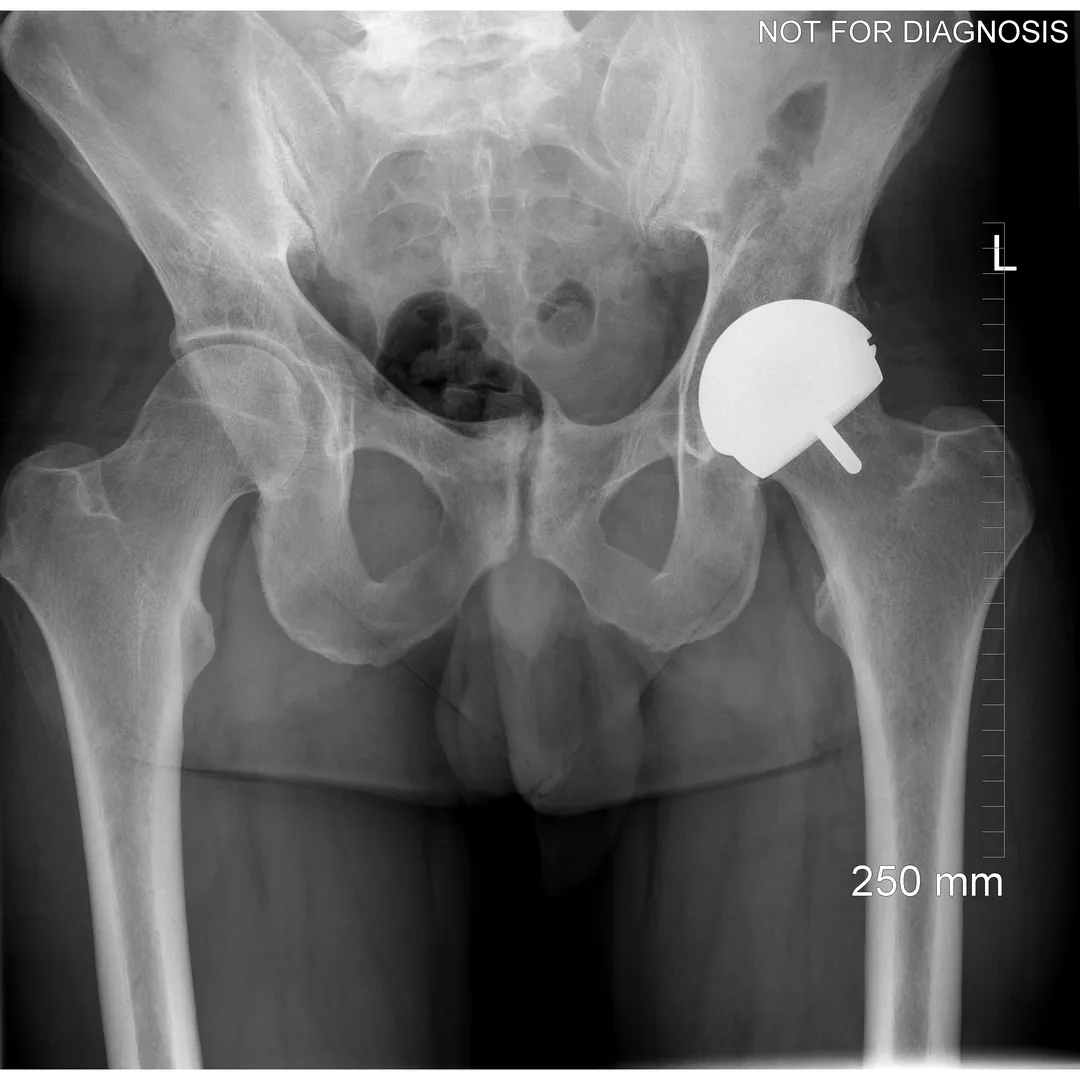

Hip resurfacing is a type of hip surgery used to treat hip arthritis, most commonly in younger and more active patients. Unlike a total hip replacement, hip resurfacing preserves more of your natural thigh bone. Instead of removing the entire femoral head (ball at the top of the thigh bone), the damaged surface is trimmed and covered with a smooth metal cap. The hip’s socket on the pelvis is also fitted with a metal cup.

Dr Grammatopoulos will review your X-rays and other imaging carefully to determine whether hip resurfacing is an appropriate option for you.